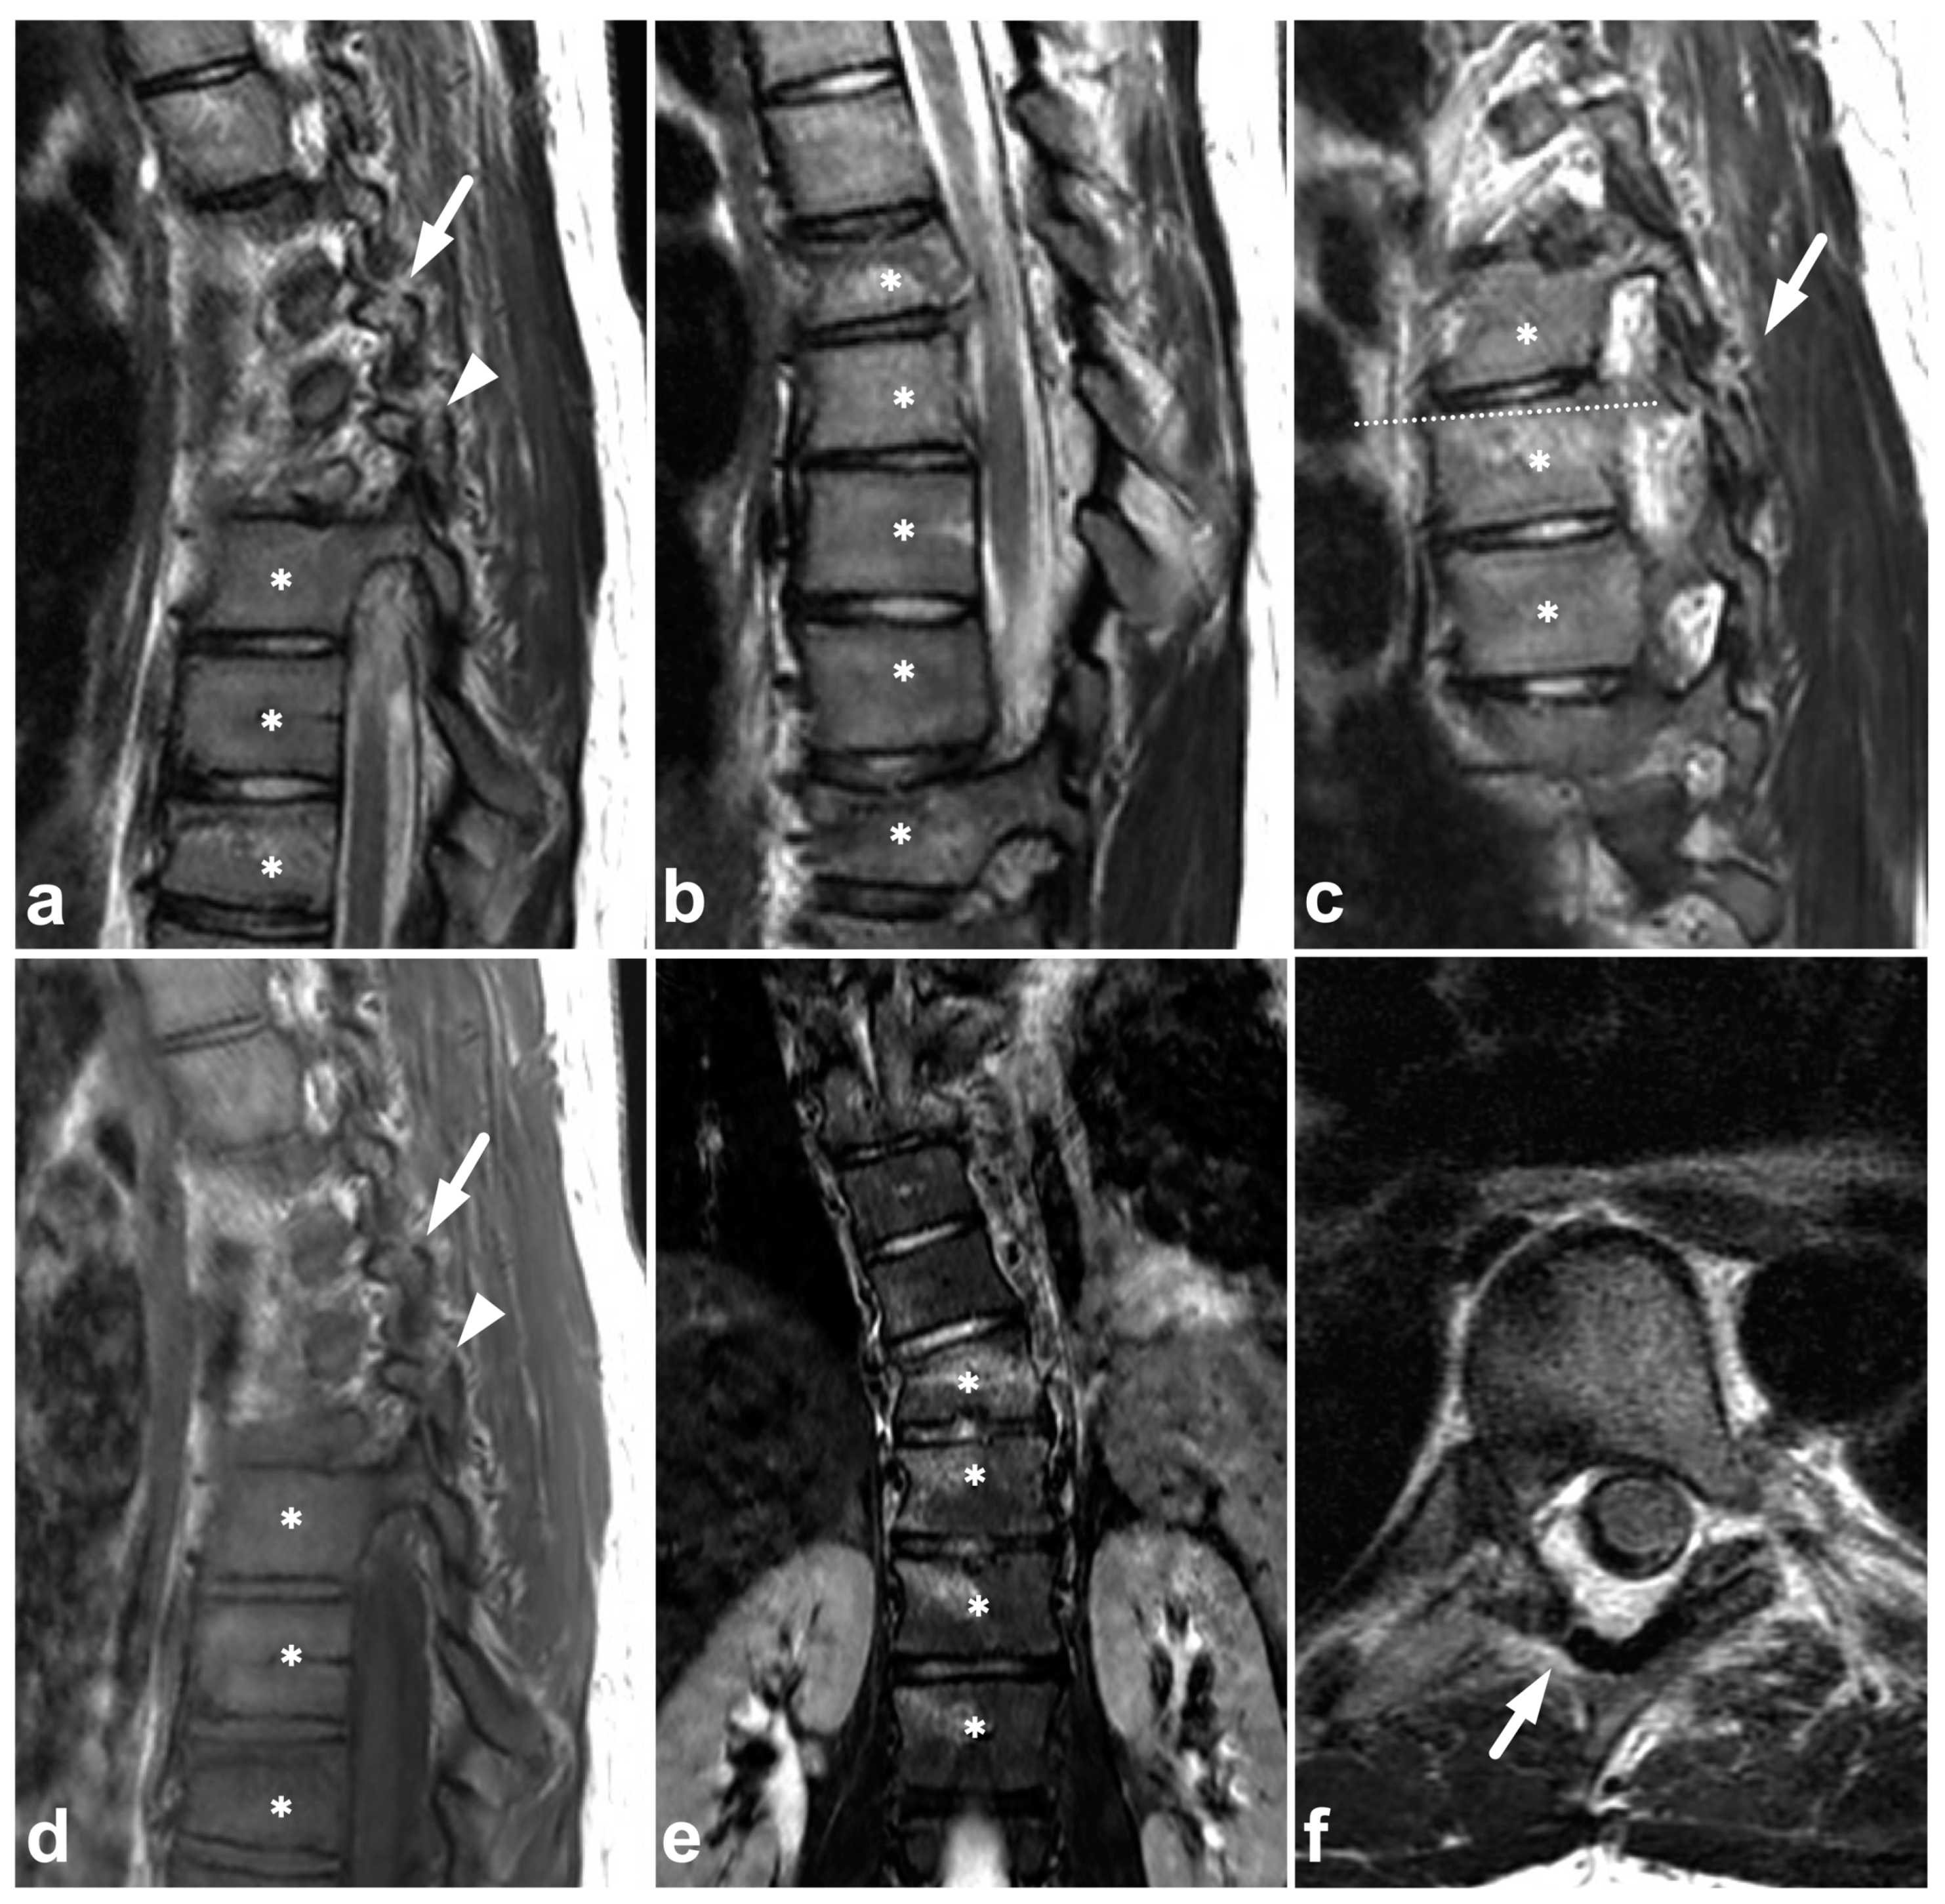

4.2. Posterior Ligament Complex